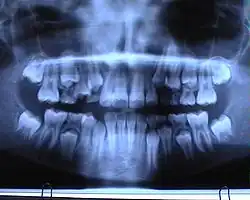

OPG eines Erwachsenen

Ein Orthopantomogramm (OPT oder OPG, seltener OPTG), auch Panoramaschichtaufnahme (PSA) genannt, ist eine zweidimensionale Röntgenaufnahme des Ober- und Unterkiefers in Form eines Halbkreises von einem Ohr zum anderen. Es ist ein Standardverfahren der dentalen Radiographie und erlaubt eine diagnostische Röntgenaufnahme der Ober- und Unterkiefer des Menschen, dabei werden alle Zähne, die angrenzenden Kieferbereiche, beide Kiefergelenke und ebenso die rechte und die linke Kieferhöhle abgebildet. Das OPT erfasst ferner den seitlichen Halsbereich, so dass auch Arterienverkalkungen der großen Halsschlagadern diagnostizierbar sind.

In erster Linie dienen OPG-Aufnahmen der Übersicht, demnach einer Grobdiagnostik, beispielsweise ob Zähne verlagert, retiniert oder nicht angelegt sind. Auch Veränderungen des Kieferknochens sind erkennbar und oft der Verlauf des Nervus mandibularis. Zahlreiche Nebenbefunde können erfasst werden. Der mittlere Bereich der Aufnahme wird durch eine verfahrenstechnisch bedingte Überprojektion der Halswirbelsäule speziell im Frontzahnbereich verschattet. Ebenso werden oft die Wurzelspitzen durch eine Überprojektion des knöchernen Gaumens verschattet. Dadurch sind diese Bereiche undeutlich abgebildet und einer präzisen Diagnostik nicht zugänglich.[6]